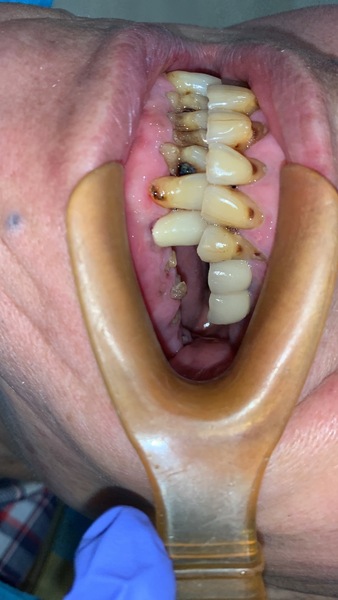

因距此位患者前一次修復牙齒已十幾年了,患者十幾年來放任牙齒不管,斷了就放著不理,或者拔牙後就不修復。

所以牙齒多處局部都受力過大,有斷裂風險。

前兩年患者認為自己身體狀況不好,決定牙齒只要壞了,就用活動假牙就可以,不想再花時間和金錢修復牙齒,太累太辛苦了。

奈何牙齒每況愈下,抽了神經後,陸續斷牙,直到累計滿5顆,真的無法再忍耐了。

於是回頭詢問醫師:有沒有什麼方法,可以讓自己可以咀嚼食物,連肉類都沒辦法吃了?